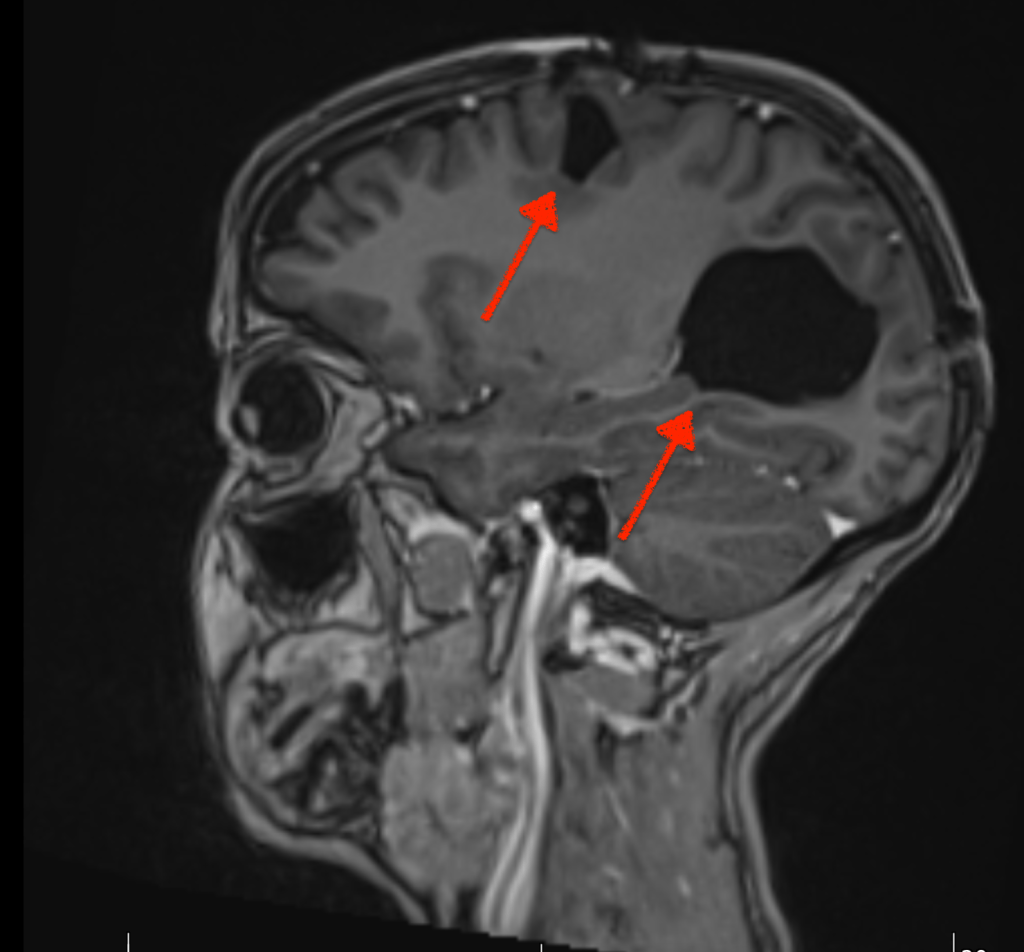

Zoë and only Zoë (as one of her oncologists reminded me) can decide. My role as advocate is to research treatments, make flow charts and advise her. She can, of course take advice from others; I guess doctors would be a good start. Sometimes, I have lost sight of her ability to make the right decision for herself; maybe focusing on the fact that she has had two chunks of her brain removed and acquired a brain injury in the process. Shocking as these images are, the surgeon may have removed the neurons that processes her right peripheral vision; but not her ability to make a decision. The brain is a fascinating organ.